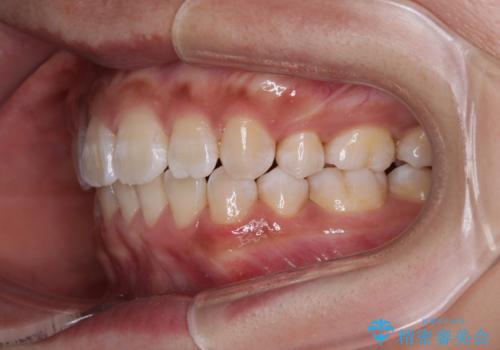

くちばしのような前歯 抜歯矯正で口を閉じやすく

- 前歯の突出感を気にして来院された患者様です。

咬合力が非常に強く、咬合力で前歯が前方に押し広げられており、上下唇に閉じにくさが認められました。

上下左右の第一小臼歯4本を抜歯し、ワイヤー装置にて矯正治療を行うこととしました。

強い咬合力により前歯の隙間がなかなか閉じられず、治療期間は長いものとなりましたが、横顔の印象が大きく変わるほど口元の印象を改善することができました。